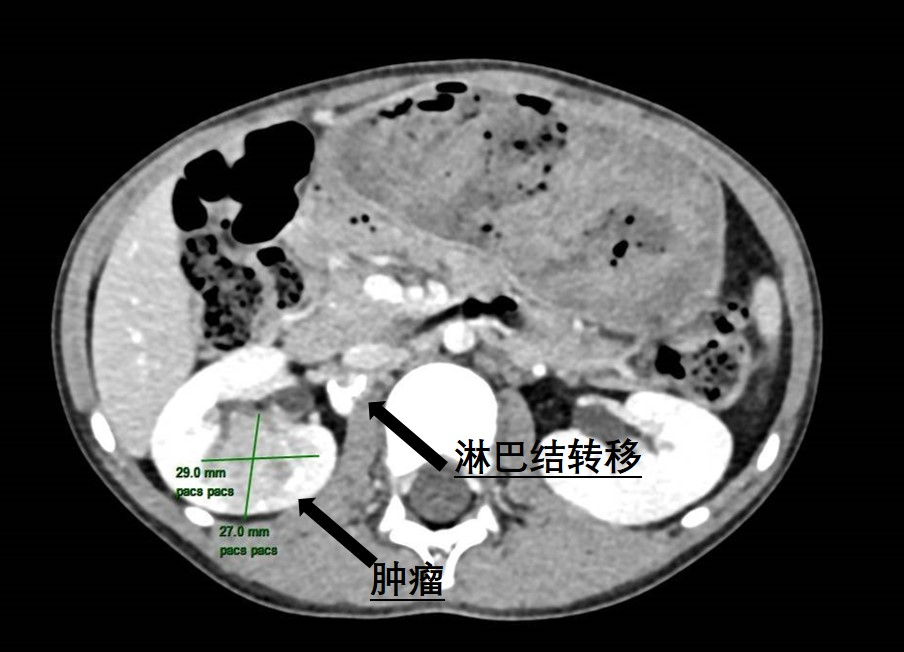

近日,捆绑调教 (简称捆绑调教 )泌尿外科为一名6岁患儿成功实施了腹腔镜下右侧肾肿瘤根治性切除伴转移淋巴结清扫手术,帮助患儿切除了罕见肾脏肿瘤。不久前,朵儿(化名)的妈妈无意中发现女儿反复血尿,这让全家人都陷入了焦虑与不安。为了尽快查找原因,朵儿妈妈带着女儿来到捆绑调教 就诊。当天,她们刚好碰上捆绑调教 的大型健康义诊活动,于是便找到了泌尿外科主任曾钦松教授问...